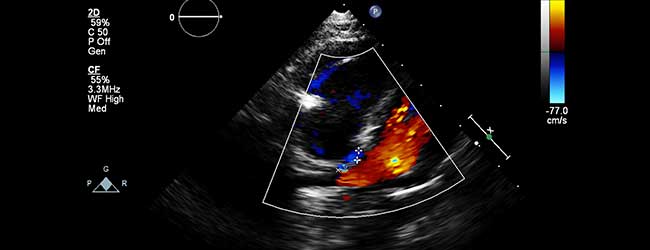

Le DZQJ008 est un acte d’échographie (code de regroupement : ADE) dont le libellé est : « échographie-doppler transthoracique et échographie-doppler par voie transœsophagienne du cœur et des vaisseaux intrathoraciques ».

C’est un acte remboursable qui n’est pas soumis à une demande d’entente préalable ; il est valorisé à 160,11 €…